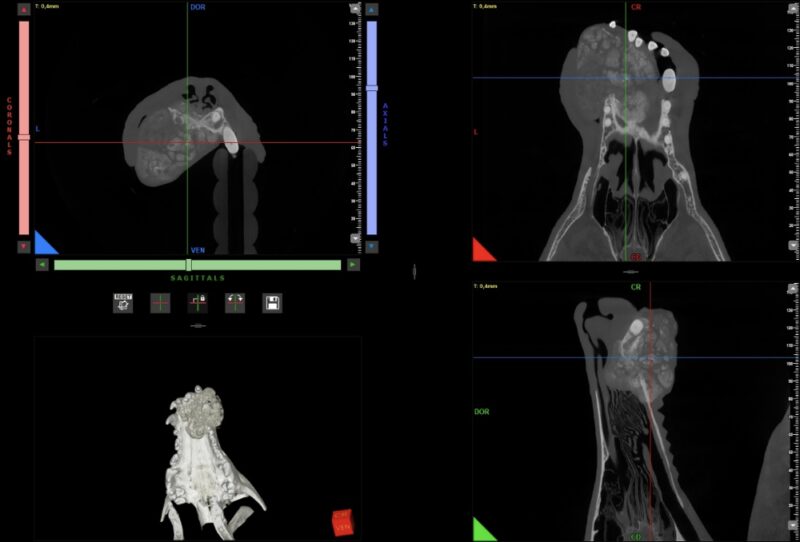

Wegen der klinisch sichtbaren Progression erfolgte die erneute Vorstellung zur weiterführenden Bildgebung. Die durchgeführte CBCT-Untersuchung zeigte eine große, heterogene, überwiegend osteoproduktive Masse des vorderen Oberkiefers. Der Tumor infiltrierte die linke Nasenhöhle, überschritt die Mittellinie und führte zu ausgeprägten knöchernen Destruktionen mit Verlagerung der Schneidezähne. Hinweise auf eine pulmonale Metastasierung ergaben sich in der Thoraxdiagnostik nicht. Das präoperative klinische Staging wurde als Stadium III (T3b, N0, M0) eingestuft. Trotz der ungünstigen Befundlage wurde nach ausführlicher Aufklärung der Besitzer eine operative Therapie angestrebt.